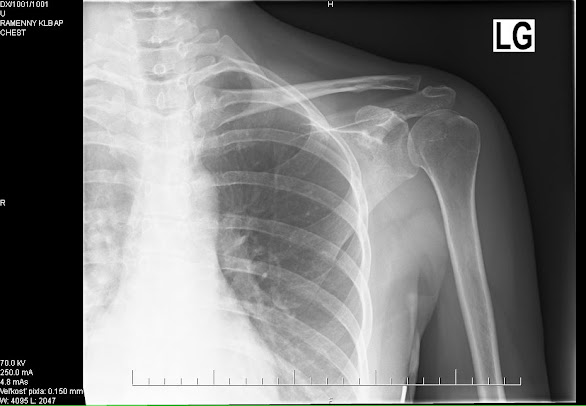

Impingement syndróm. Diagnóza podľa sonografického

vyšetrenia. Laický popis je taký, že tam niekde v ramene, blízko

kĺbu, mám výrastky, tie mi tlačia, alebo

privierajú nervy pri pohybe.

syndróm. Poslal ma na rengen, ten som stihla na otočku a okrem iného vraj

mám aj zodratú platničku niekde v krku, medzi 6. a 7. stavcom. Tým sa

Jednoznačne a zreteľne vytŕčajúca ľavá lopatka. Nedrží na svojom mieste, ale hýbe sa s rukou. Tak kosť stále pri cvičení vychádza pod pazuchou. Maximálny zdvih ruky po zákroku:

V októbri som ruku už podstatne lepšie natiahla. No kosť lopatky stále vychádzala von. Rotátorová manžeta nepracovala ako mala, jej svaly bolo ochabnuté a nedržali ju: